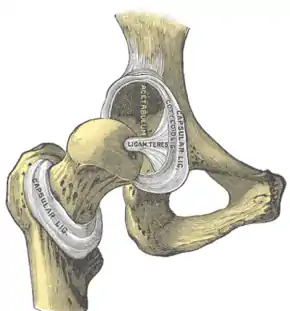

Hip-joint, front view. The capsular ligament has been largely removed. (Cotyloid lig. visible at center.) | |

The acetabular labrum (glenoidal labrum of the hip joint or cotyloid ligament in older texts) is a fibrocartilaginous ring[1][2][3] which surrounds the circumference of the acetabulum of the hip, deepening the acetabulum. The labrum is attached onto the bony rim and transverse acetabular ligament. It is triangular in cross-section (with the apex represented by the free margin).[2][3]

The labrum contributes to the articular surface of the joint[2][1] (increasing it by almost 10%[1]). It embraces the femoral head,[2] holding it firmly in the joint socket[3] to stabilise the joint. It thus also seals the joint cavity, facilitating even distribution of synovial fluid so that friction is reduced and dissolved nutrients are better distributed.[2]